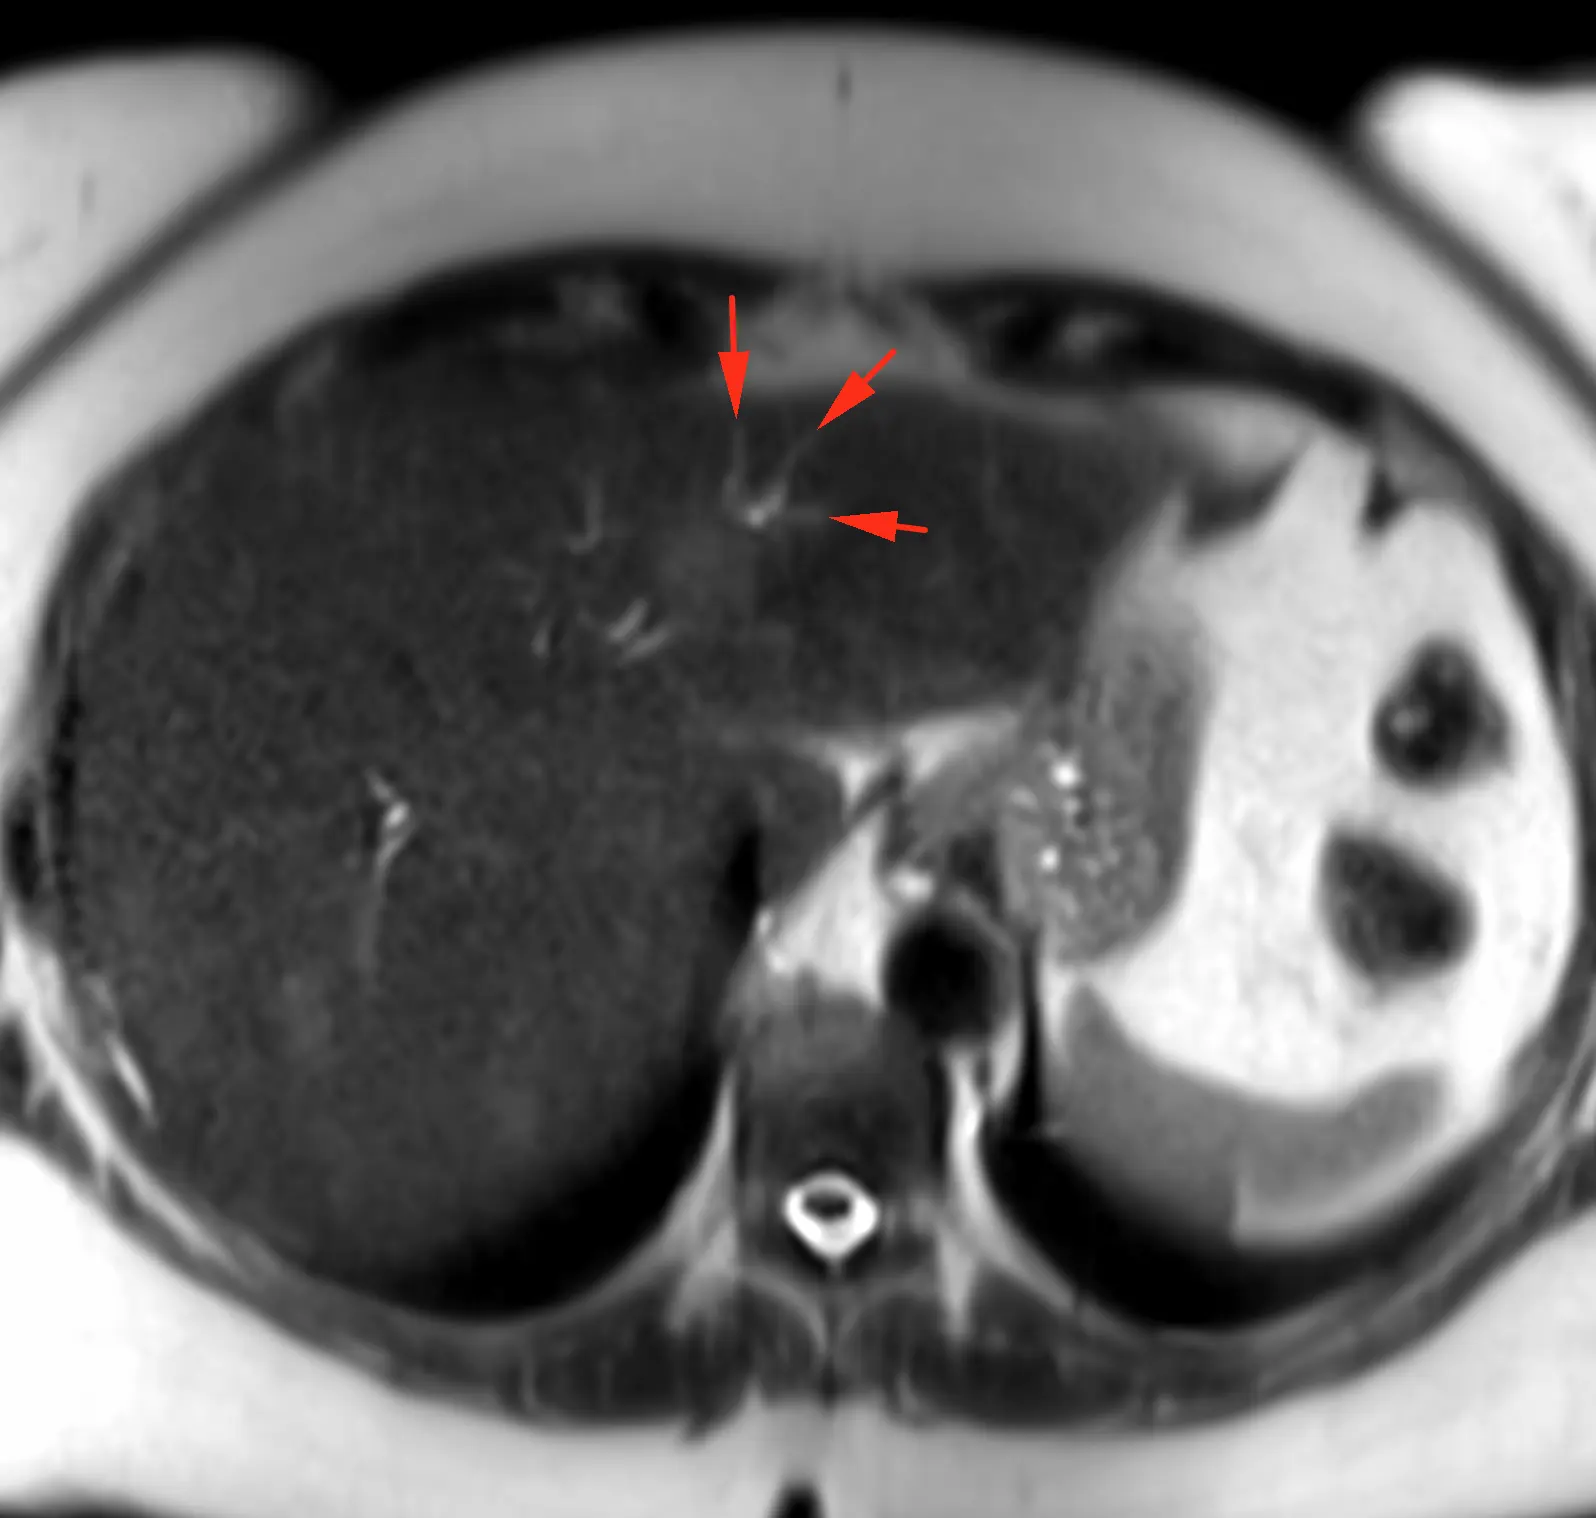

ЖЕНЩИНА 38 лет, фокальное изменение печени выявлено на УЗИ.

Повторные #КТ (с разницей в 2,5 месяца) без динамики. Имеется медленное, постепенное, слабоинтенсивное накопление контраста от периферии к центру.

На #МРТ - очень высокий сигнал на Т2, низкий на Т1, «лучистые» контуры. Истинное ограничение диффузии (ADC=460±109х10-6 кв.мм/с). Накопление контраста такое же, но на МРТ лучше видны краевое узелков накопление в артериальную фазу, тотального контрастирования нет даже на отсроченной фазе (через 5 минут).

Картина характерна: это гиалинизированная/ #склерозированнаягемангиома. Характерное стяжение контура является свидетельством склерозирования: уменьшения объёма, «рубцевания».

Гемангиомы с суженными кавернозными пространствами из-за склероза имеют большее количество более толстых и неровных перегородок, которые могут препятствовать диффузии молекул, что приводит к снижению значений ADC.

Склерозированные гемангиомы печени — это редкие доброкачественные поражения, которые часто трудно отличить от злокачественных, ибо они не имеют типичных для кавернозных гемангиом признаков.

Но! Часть признаков все равно сохраняются:

1. Значительный гиперсигнал на т2

2. Резкие, хоть и неровные, контуры

3. Центрипетальное, и иногда с приставочными узелками накопления контраста на артериальной фазе, контрастирование, пусть и неполное.

4. Стабильность в динамике